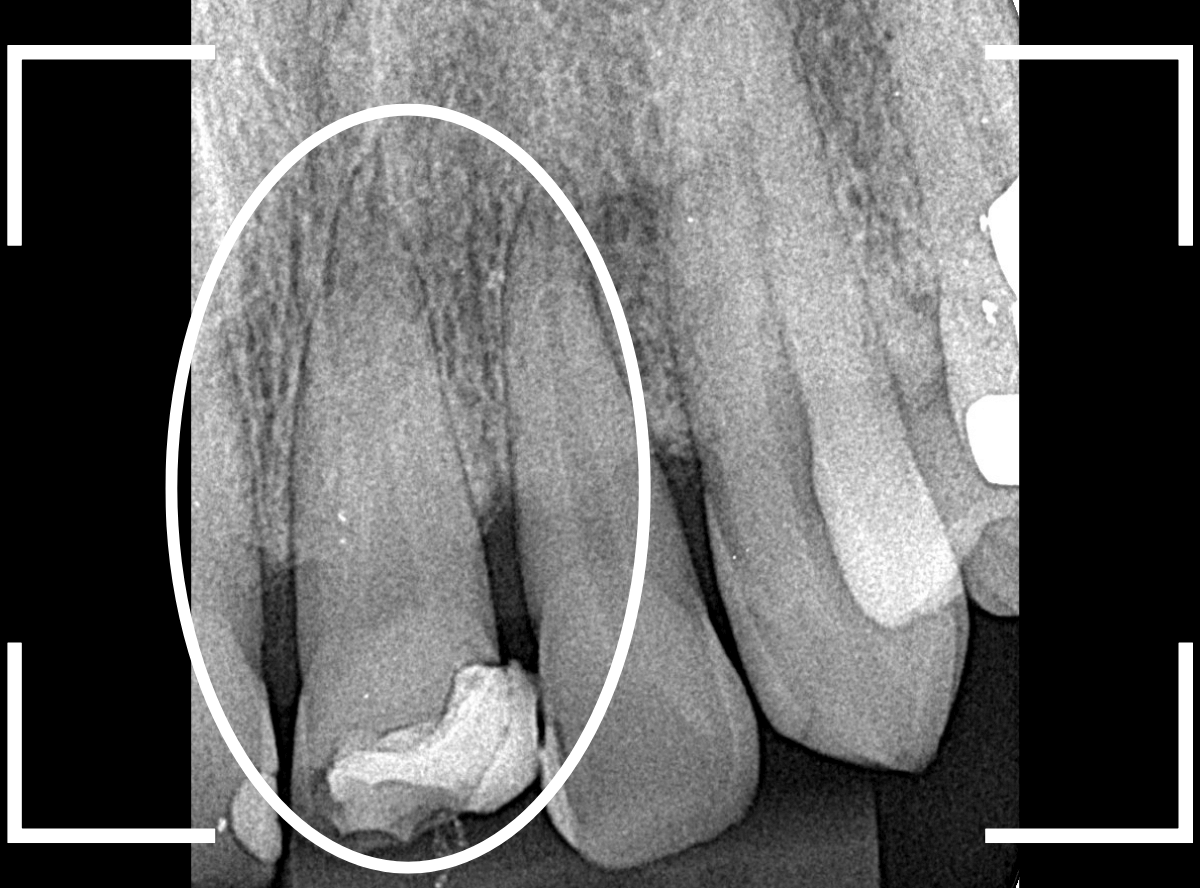

Case.4 <動画編>深い虫歯が進行したさし歯を、セラミックで何とか治療したケース

今回は、深い虫歯が進行してしまったさし歯をセラミックで治療し直したケースをご紹介します。

検査をすると、さし歯の周りの歯肉から出血が多いため、レントゲン写真で確認すると、さし歯の中で虫歯が進行していると診断されました。

神経を取っているさし歯の中の虫歯は、レントゲン写真でも正確にはわからず痛みもないため、さし歯をはずしてみないと、どれくらい進行しているかははっきりわかりません。 虫歯と診断されたさし歯の中は一体どうなっているのでしょうか?

ぜひ、ご覧ください。